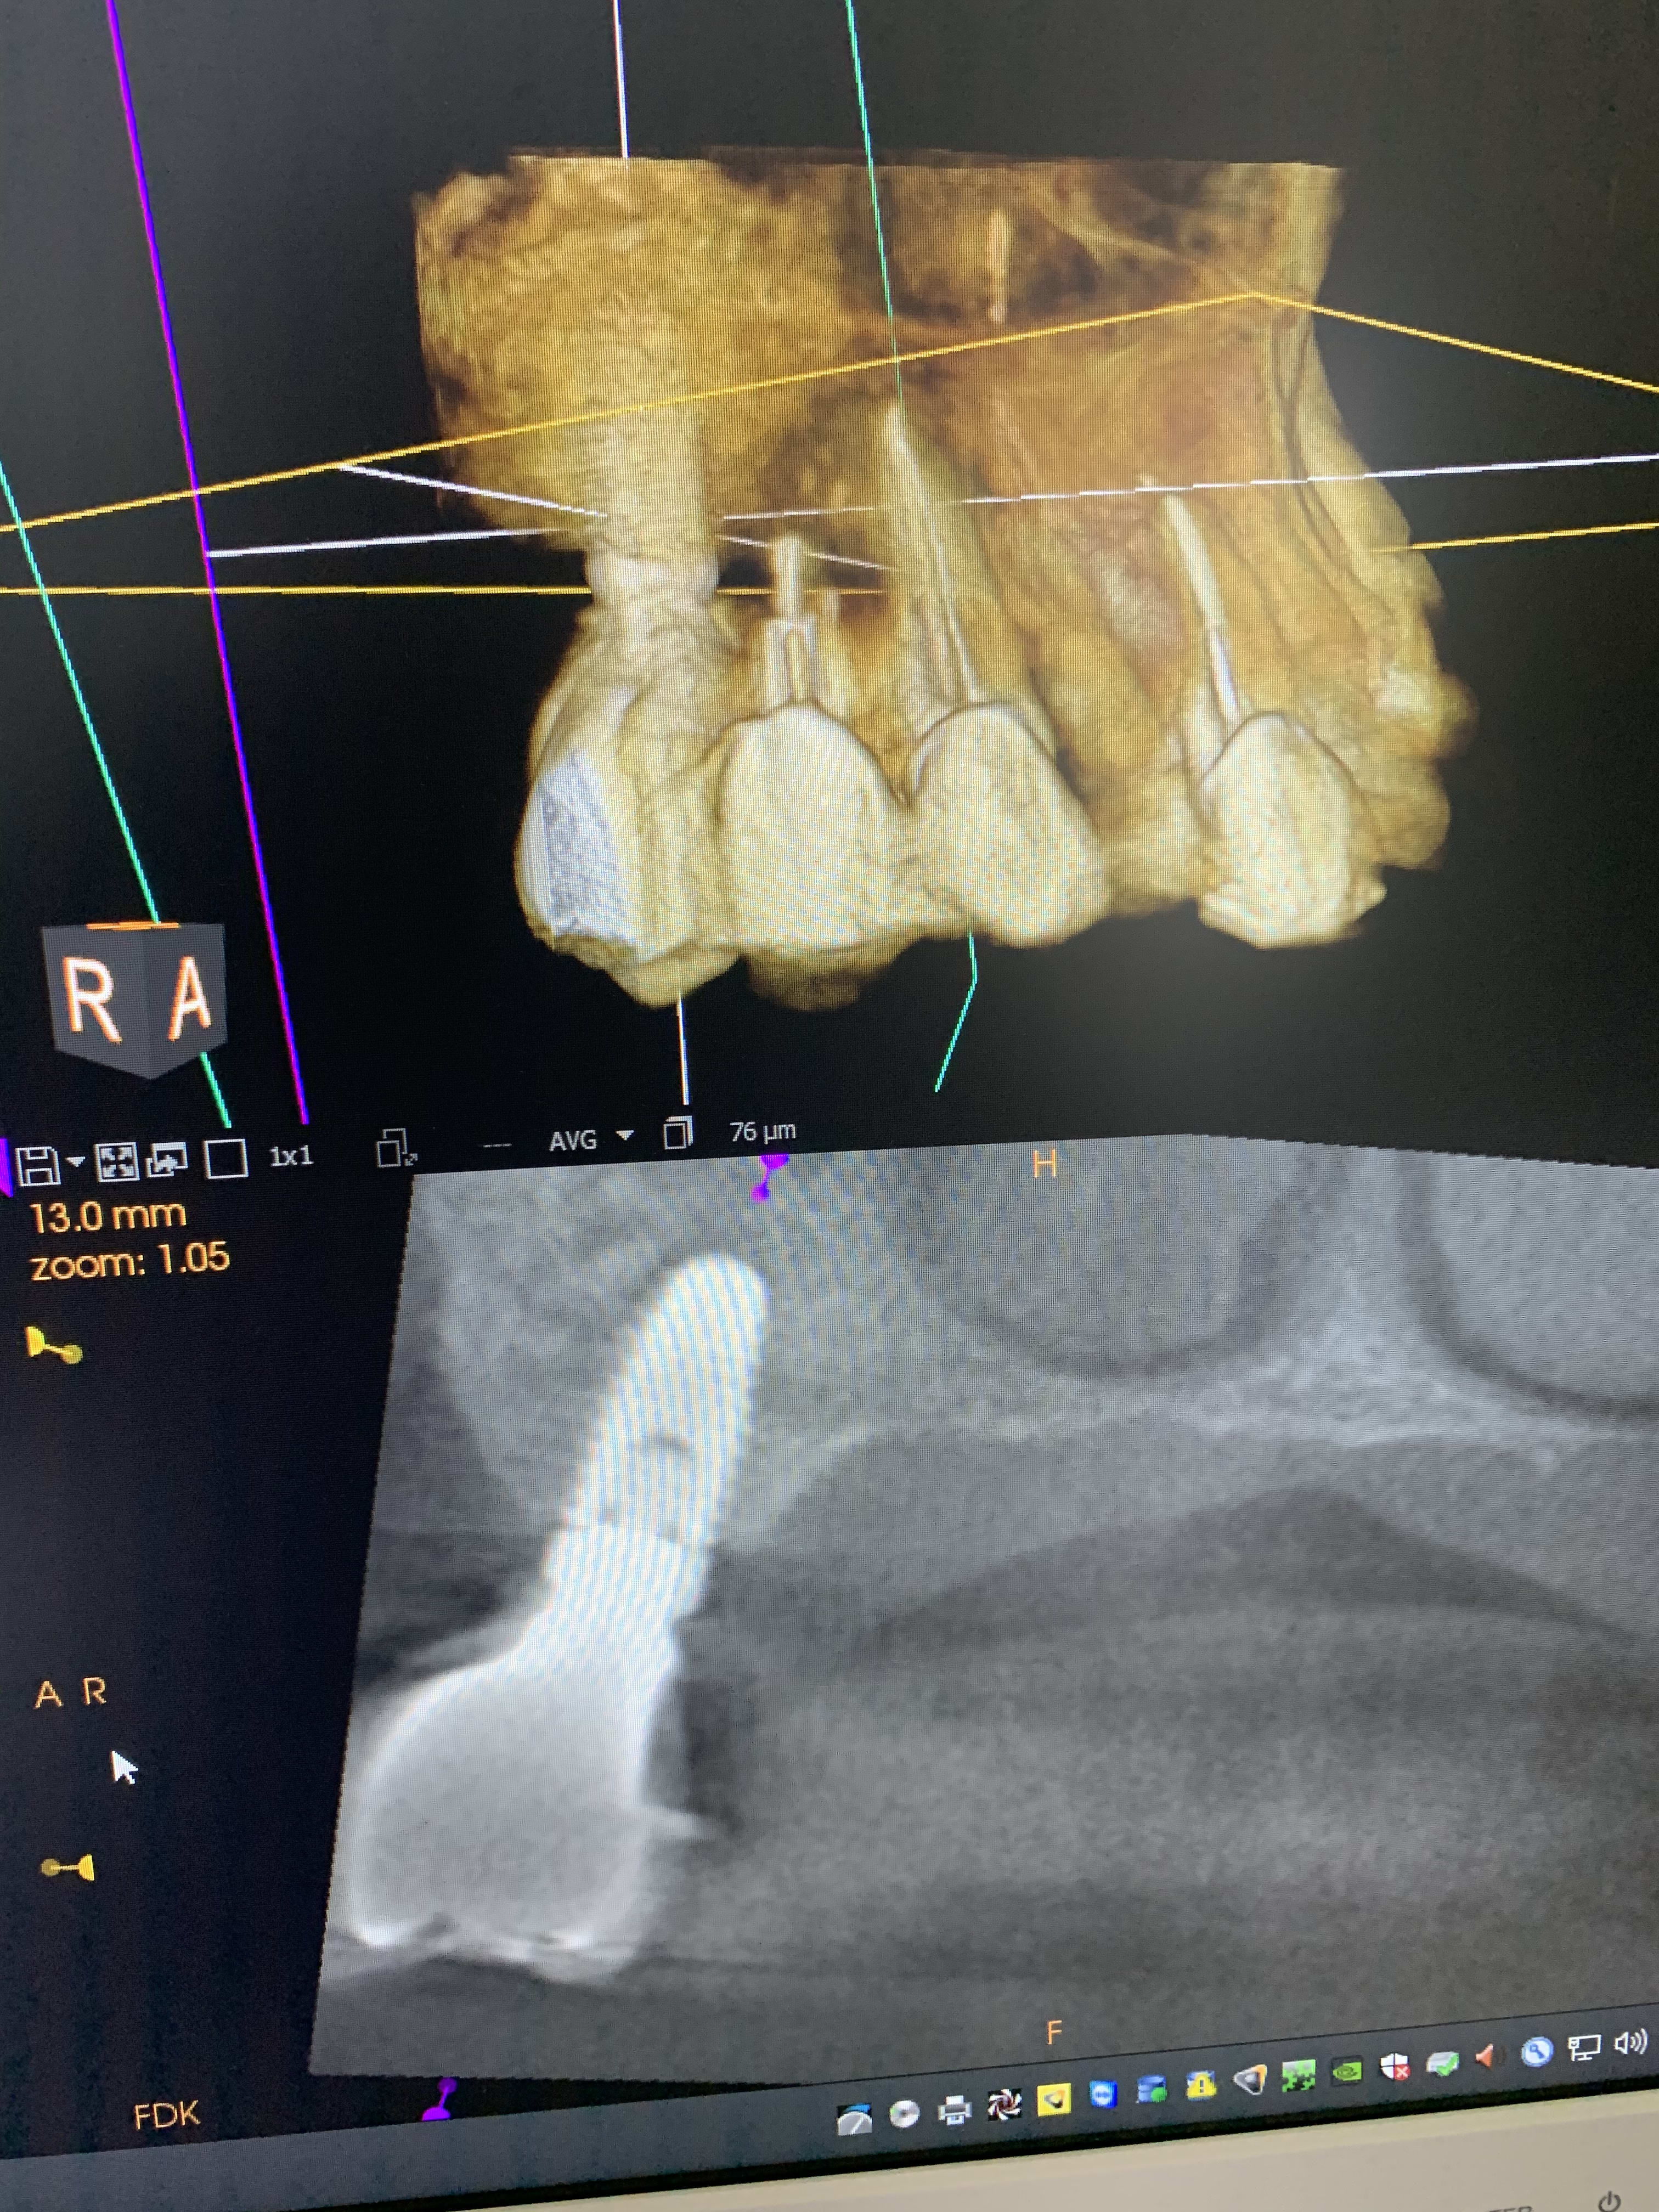

Il y a vraiment des différences de dingue entre les machines !

Les images 3 et 4, les images 6 et 7 sont prises à quelques années d’intervalles.

La machine de 2008 fait très peu d’artefacts, celle de 2018 énormément. Elle à le mar pour les « supprimer », mais ça n’arrange rien !

Une machine est de 2008, l’autre de 2018, même marque.

A l’adf on me dit « regardez on voit même les spires des implants », avec ma bécanne de 2008 je vois les spires des vis dans les implants, les têtes de vis... je n’ai rien vu d’équivalent sur les machines récentes.

Regardez comme les tenons sont bien trop larges à la radio !

Les implants sont de gros pâtés blancs...